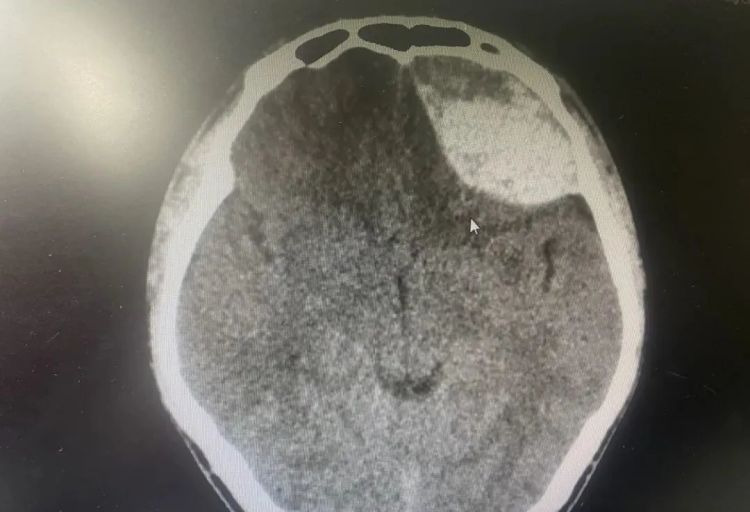

2024年6月,云南罗平县的小张同学打篮球时不慎滑倒,左侧头部受伤。头颅CT显示颅内未见明显挫伤及出血,清洗伤口后他便返回家中观察。

3天后,小张突发头昏头痛,伴恶心呕吐、食欲减退,家属立即送其就医。经检查,确诊为左侧额部硬膜外血肿。因颅内出血量较大,他被立即送入手术室,术后康复出院。

图源:罗平县中医医院